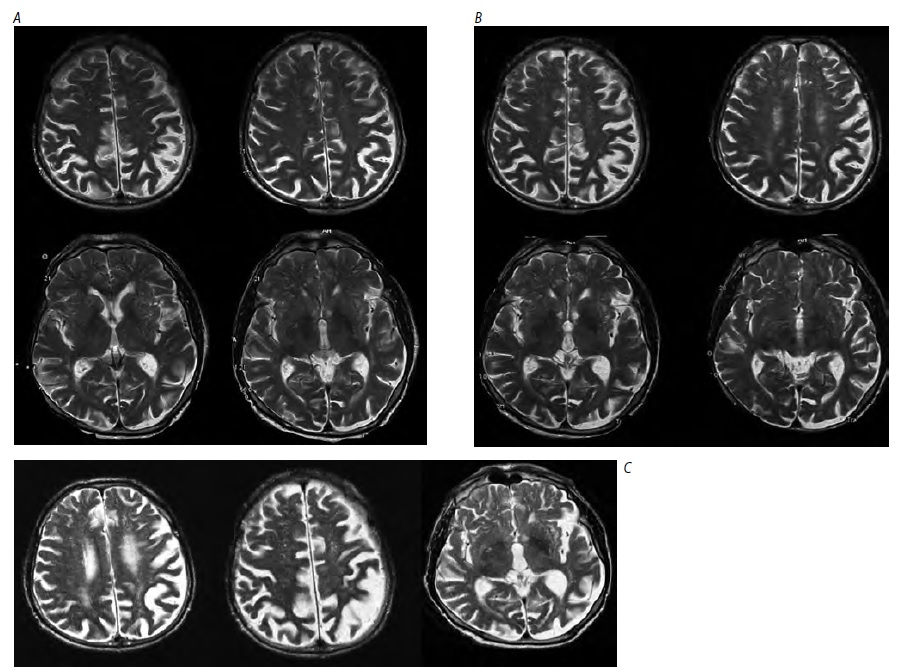

Пациент В., 81 года, наблюдался нами в течение 2 лет. На момент первичного осмотра обращала на себя внимание трудность подбора слов в разговорной речи при практически полном отсутствии других когнитивных нарушений, затруднения при повторении слов и предложений. В неврологическом статусе определялись отдельные микросимптомы. По данным МРТ головного мозга от октября 2016 г. были выявлены очаговые изменения сосудистого характера, умеренные атрофические изменения (рис. 6, А). При детальной оценке томограмм выявлена лёгкая асимметричная атрофия коры головного мозга за счёт левой височно-теменной области. Нейропсихологическое тестирование: MMSE — 27 баллов, FAB — 15 баллов, литеральные ассоциации — 12 слов, категориальные ассоциации — 14 слов. Тест рисования часов — 8 баллов.

Рис. 6. МРТ-изображения головного мозга пациента со смешанной формой ППА с последующим развитием клинически значимого кортико-базального синдрома. А — МРТ головного мозга 2016 г.; В — 2017 г.; С — 2019 г. / Fig. 6. Brain MRI of a patient with mixed PPA and subsequent development of clinically significant corticobasal syndrome. А — brain MRI in 2016; В — in 2017; С — in 2019.

В течение года клиническая картина неуклонно прогрессировала. Речь постепенно теряла свою беглость и плавность, требовала всё больших усилий, снизилась речевая активность. Пациент стал немногословным, старался избегать лишних высказываний, чтобы скрыть свой дефект. Говорил короткими фразами, часто не связанными между собой, используя преимущественно существительные при минимальном включении прилагательных. При повторном МРТ-исследовании выявлено значительное увеличение выраженности асимметричной левосторонней атрофии височной и теменной доли (рис. 6, В), что характерно в большей степени для лППА. Клинически вышеуказанная симптоматика при этом расценивалась в рамках аППА, однако также присутствовали отчётливые затруднения при повторении предложений, в том числе коротких и простых.

По прошествии 2 лет пациент полностью утратил способность к речевой продукции, однако понимание обращённой речи было полностью сохранено. Обратило на себя внимание появление апраксии правой руки, постоянное двигательное беспокойство правой кисти. Кроме того, при осмотре отмечено появление и других синдромов: лобной апраксии, в том числе апраксии ходьбы, асимметричной экстрапирамидной ригидности с гемипаркинсонизмом; миоклонуса правой руки; идеаторной апраксии в обеих руках; тяжёлых когнитивных нарушений, проявляющихся, в первую очередь, дизрегуляторными расстройствами. Нейропсихологическое обследование в 2019 г. оценить достоверно не представлялось возможным в связи с отсутствием у пациента речевой функции, при выполнении заданий с использованием письма у пациента выявлялись множественные грамматические ошибки. При этом тест рисования часов пациент выполнял верно. При оценке МРТ головного мозга выявлялась грубая асимметричная корково-подкорковая атрофия (рис. 6, С). Согласно рентгенологической шкале Global Cortical Atrophy (GCA) данные изменения соответствовали III cтепени атрофии головного мозга (по типу «лезвия ножа»).

В представленном наблюдении в дебюте заболевания клиническая симптоматика соответствовала типичной аППА, однако по мере прогрессирования заболевания появились признаки лППА, для которой характерной является развитие асимметричной атрофии височнотеменных отделов доминантного полушария. Ещё через год наряду с афатическим дефектом в клинической картине стал доминировать кортико-базальный синдром, вероятно, связанный с вовлечением в патологический процесс и подкорковых структур. Таким образом, представленный случай характеризует редкий пример смешанного варианта (сочетание аППА и лППА) ППА с последующим развитием клинически манифестной кортико-базальной дегенерации.